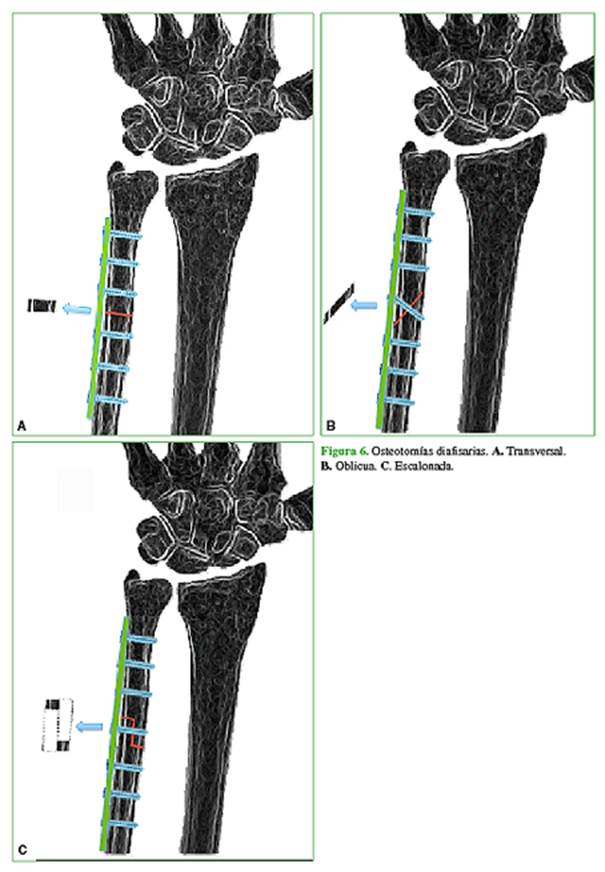

El concepto de acortamiento cubital perduró a través del tiempo, fue mejorando la precisión de los sistemas de acortamiento y osteosíntesis, y hoy en día, se considera el patrón de referencia en el tratamiento de esta enfermedad.10,16 La primera fijación de una osteotomía transversal de acortamiento con placa y tornillos fue descrita por Cantero, en 1974 (Figura 6A). Posteriormente se describieron osteotomías oblicuas que permitieron colocar un tornillo compresivo transosteotomía con el fin de mejorar la estabilidad del sistema y la tasa de consolidación (Figura 6B).

Darlis describió una osteotomía de acortamiento diafisaria escalonada cuya ejecución es bastante más compleja, pero con las ventajas de poder colocar un tornillo compresivo transosteotomía, una mayor superficie de contacto y un mejor control de la rotación. Utilizando una placa de neutralización de 3,5 mm, de ubicación volar, consiguió un 100% de consolidación en su serie de 29 pacientes (Figura 6C).